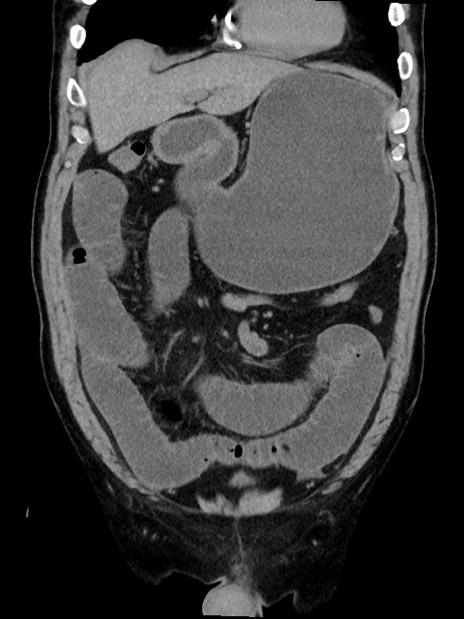

横断像

【症例】70歳代 男性

【主訴】腹部膨満、嘔吐

【現病歴】昨日より腹部膨満感出現。本日増悪し、仙痛出現。嘔吐あり、受診。

【既往歴】糖尿病、胆摘後

【身体所見】BP 149/80mmHg、HR 74/min、BT 35.9℃、腹部:膨満、軟、圧痛なし。腸雑音減弱あり。上腹部正中切開瘢痕あり。

【データ】WBC 13500、CRP 1.72